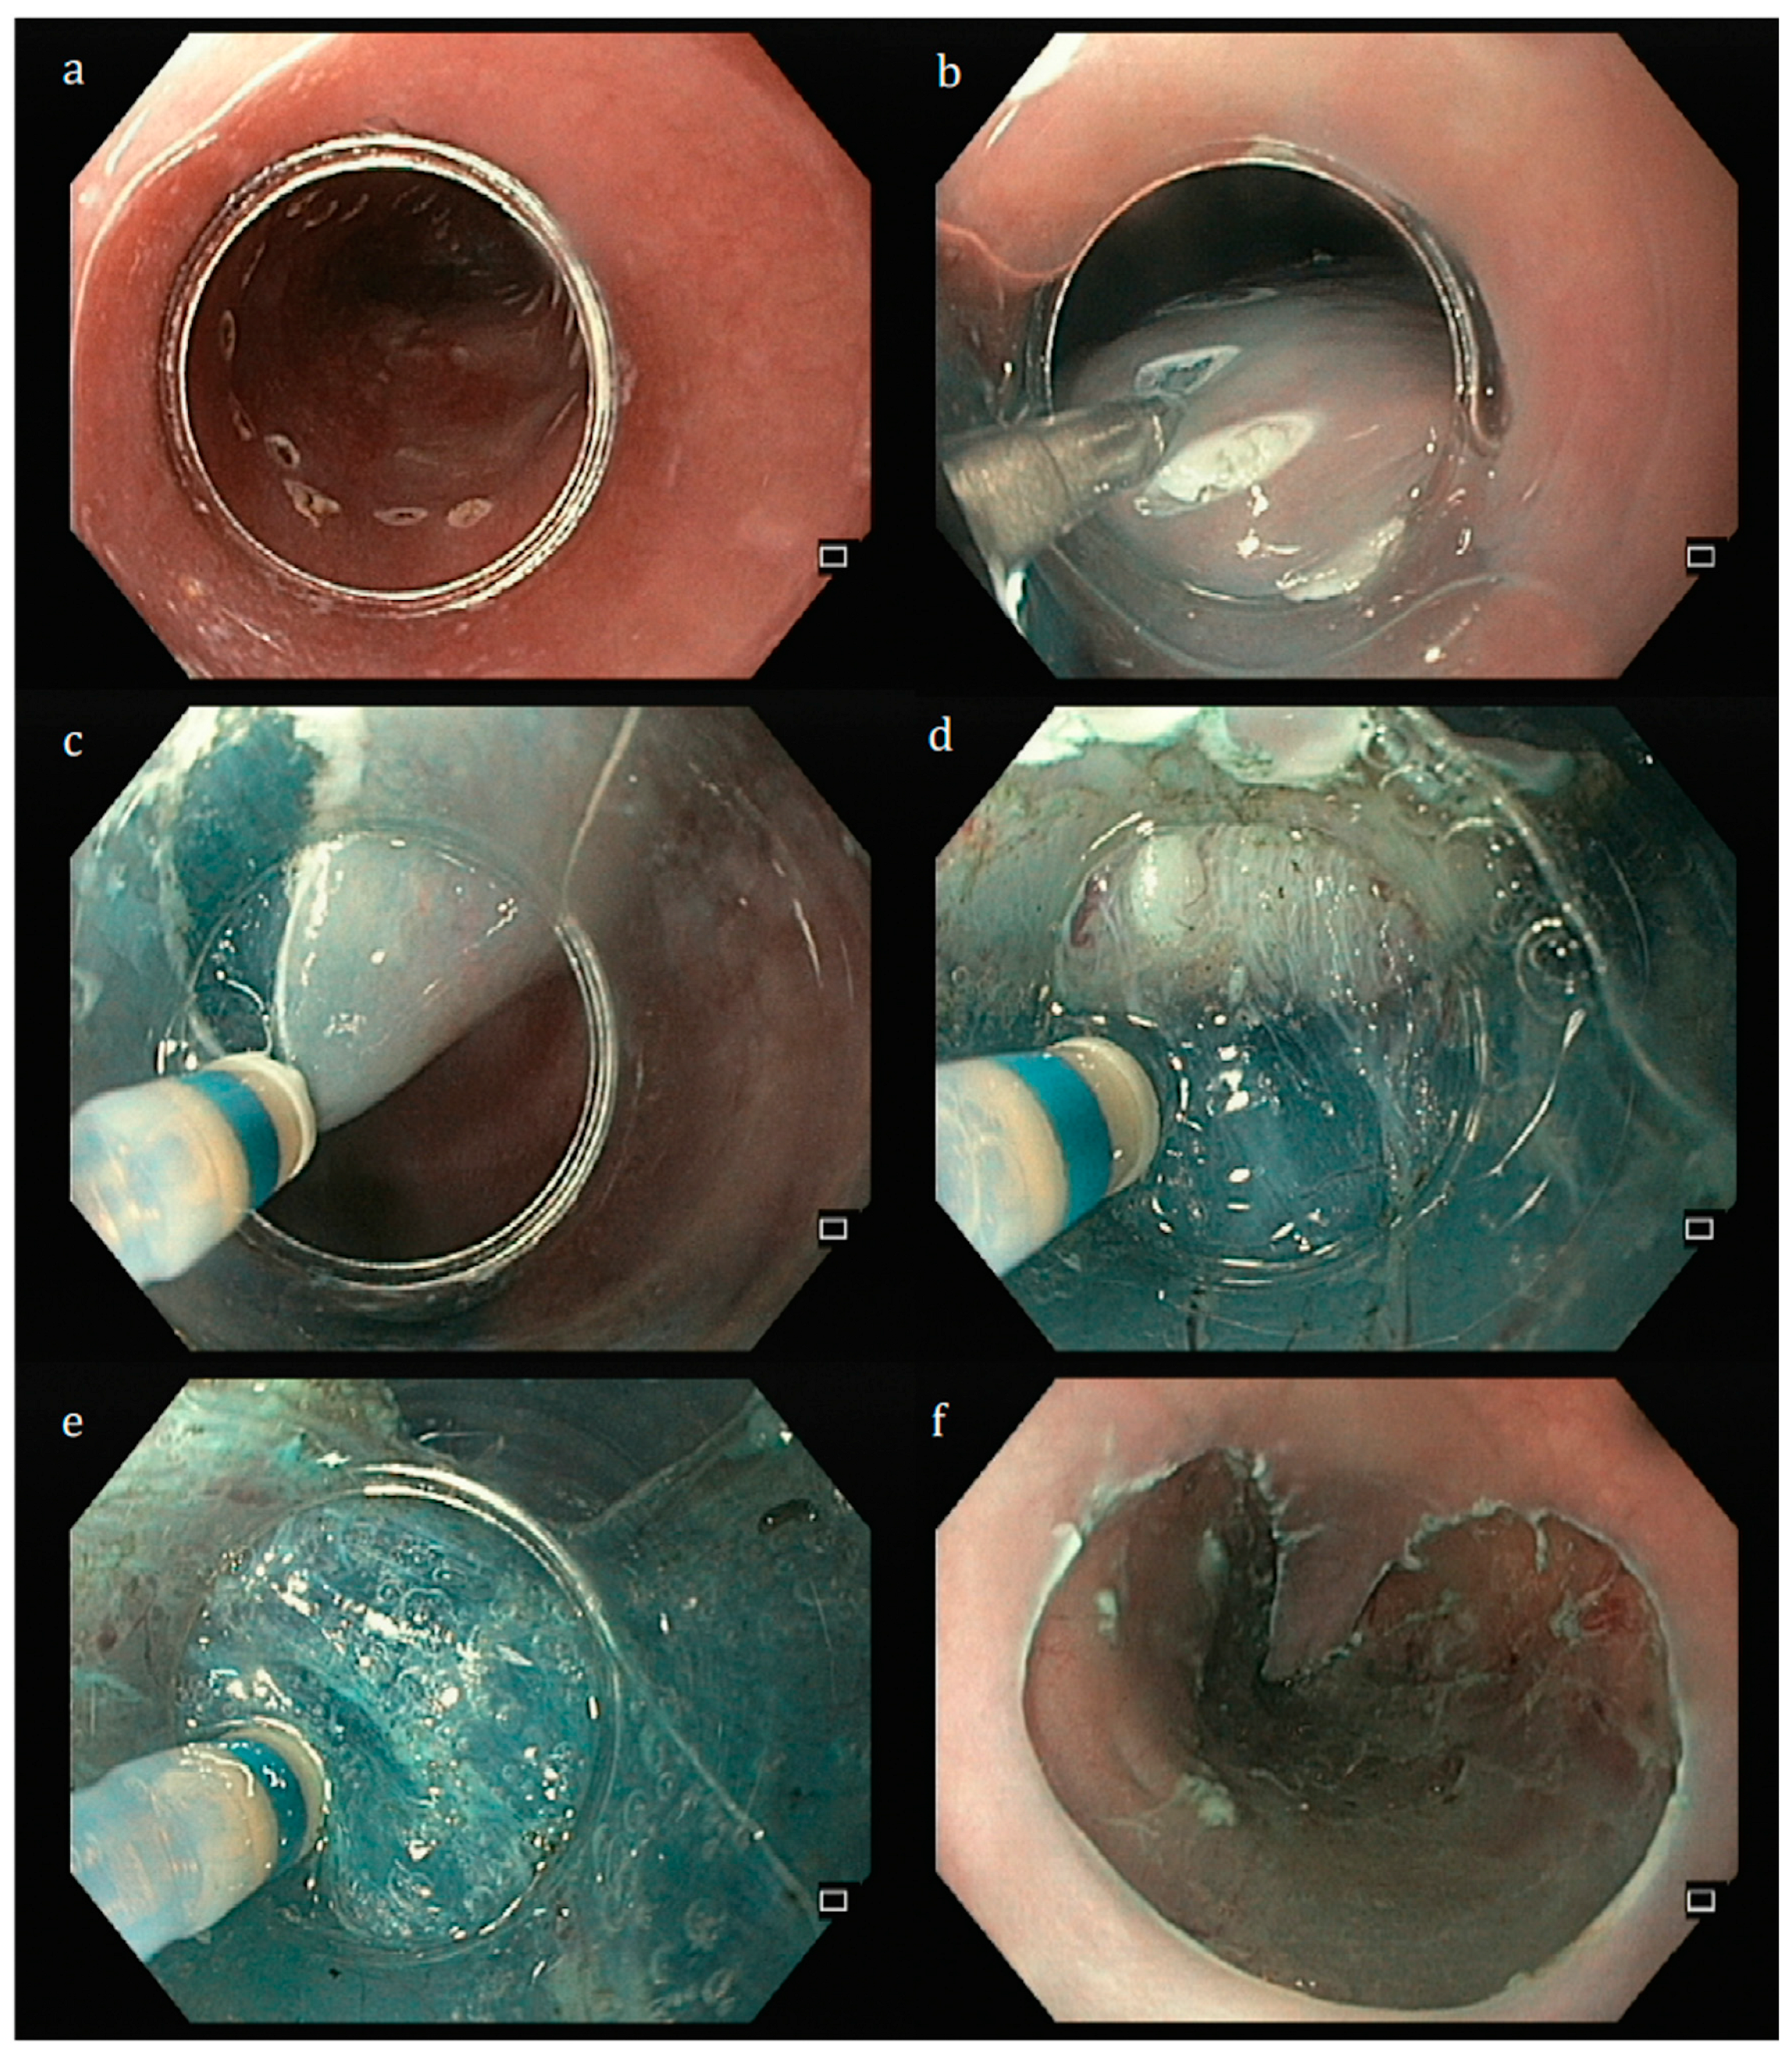

3.1. Esophagus